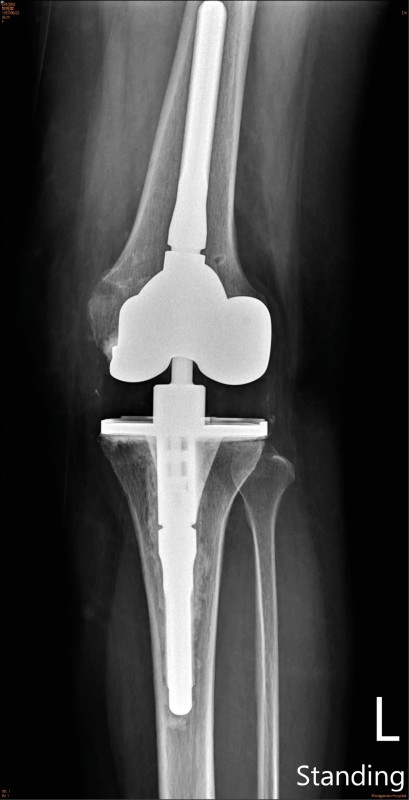

▲X光影像。(照片提供/王大翊)

手術方面,傳統全人工膝關節再置換術手術對於肌肉、韌帶、關節囊等軟組織的破壞較大,且骨質流失較多,傷口也特別疼痛。透過微創手術的概念可以減少軟組織被破壞,大幅減少骨質流失,隔天即可下床活動,約1週就能擺脫枴杖,自行行走。